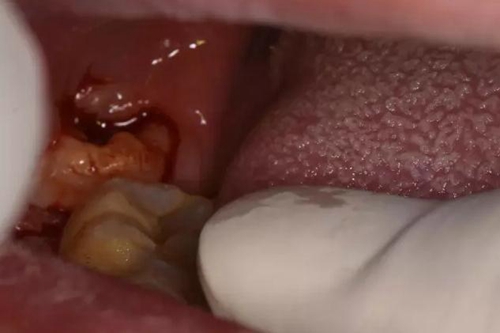

圖9.局部皮膚浸潤麻醉、在膿腫最低部位切開